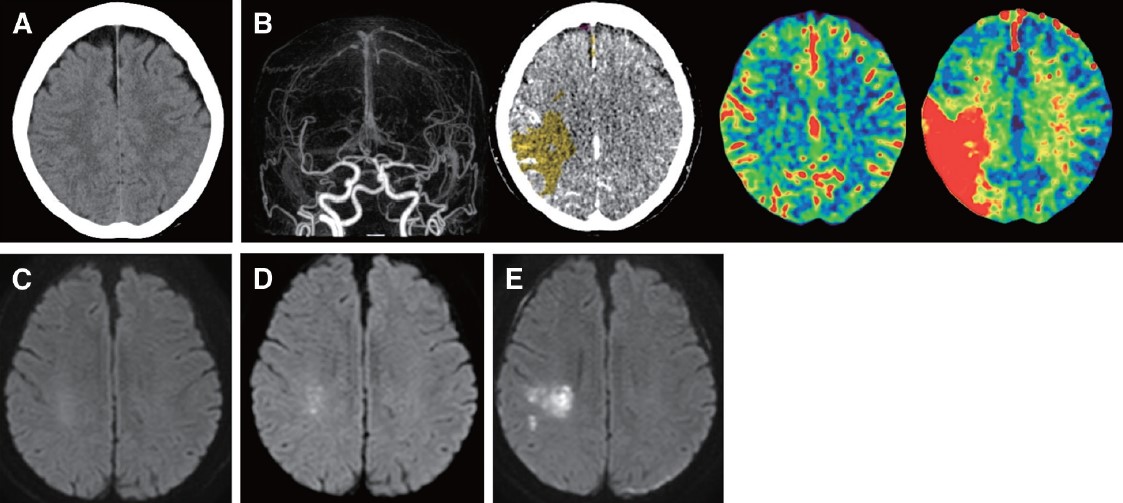

Advance Online Publication Predictive Value of Acute Neurological Progression Using Bayesian CT Perfusion for Acute Ischemic Stroke with Large or Median Vessel Occlusion doi.org/10.5797/jnet.o…

Advance Online Publication

Predictive Value of Acute Neurological Progression Using Bayesian CT Perfusion for Acute Ischemic Stroke with Large or Median Vessel Occlusion

doi.org/10.5797/jnet.o…